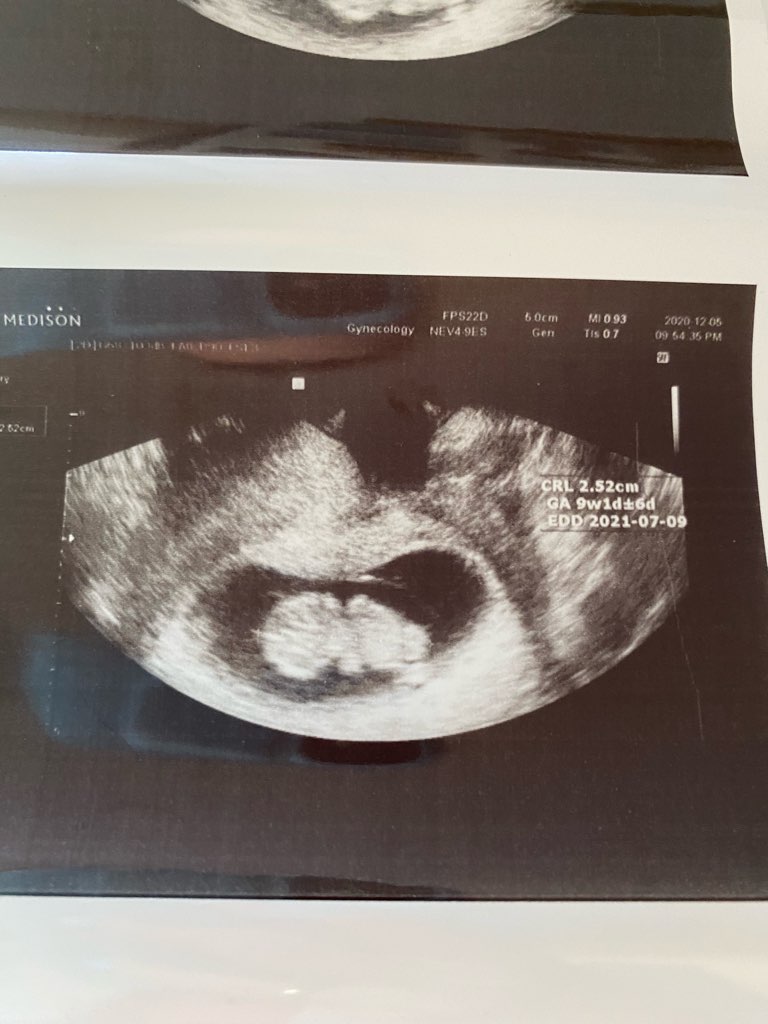

Hej dziewczyny, ja jestem po wizycie u polskiej ginekolog, niesamowite jak moja fasolka urosła przez 3 tygodnie! Już wszystko pięknie widać ❤️ Tym samym przesunął mi się termin na 9 lipca (9+1 dzisiaj). Lekarka uznała, że mogę odstawić Duphaston, ponoć on też może zwiększać mdłości.

• IMG_0265.jpg

IMG_0265.jpg

88,9 KB · Wyświetleń: 107